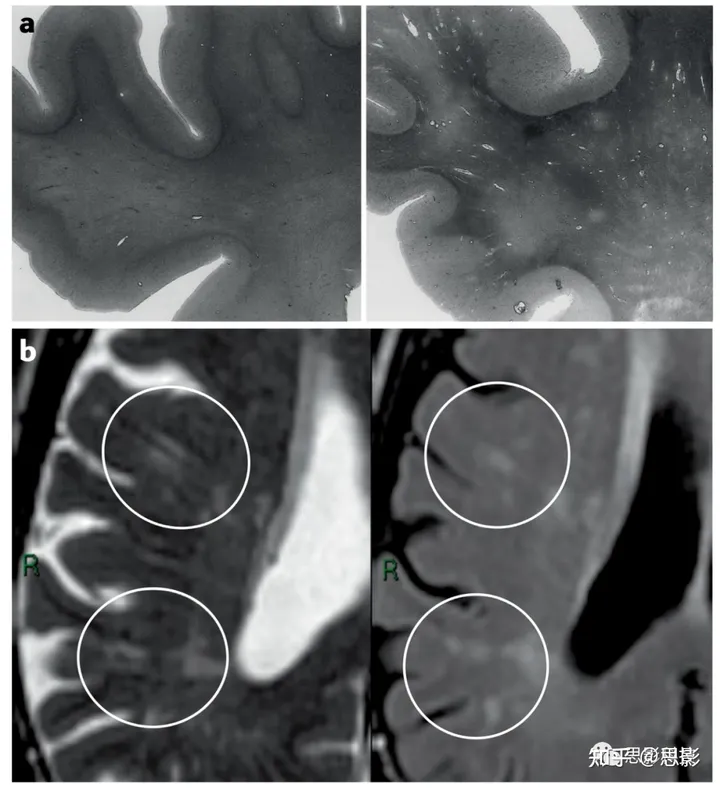

图3 血管周围间隙与小血管病。

a | 一位认知正常的74岁个体的额上回和白质切片用苏木精和伊红染色(左);未见血管周围间隙扩大。一个80岁的阿尔茨海默病患者,具有ApoE ε4/ε4基因型的类似切片(右),显示出许多动脉小球,其血管周围间隙在白质中可见,但不穿过皮质。白质中的淡色斑点是髓鞘稀疏区。放大倍数约为2.5倍。

b | 一位75岁轻度缺血性中风患者的轴向1.5-T脑MRI扫描。T2加权MRI(左)显示白质中垂直于皮质运行的众多血管周围间隙(圆圈)。液体衰减反转恢复成像(右)显示白质高信号围绕血管周围间隙开始形成,包括一些类似于线状和斑点状白质稀疏区(如a部分)的大型白质高信号(圈)。

许多横断面研究已经证明,血管周围间隙与WMHs(白质高信号)有关 — 可见的血管周围间隙越多,WMHs越严重,WMHs似乎在血管周围间隙周围形成(图3)。然而,2019年发表的一篇关于血管周围间隙与SVD病变关联的系统综述质疑血管周围间隙与WMHs是否具有横断面关联。在这个分析中包括的23项研究中,在其中对年龄和血管风险因素进行了调整,血管周围间隙与腔隙(n = 4,894,OR 3.56,95% CI 1.39–9.14,P = 0.008)和微出血(n = 5,015,OR 2.26,95% CI 1.04–4.90,P = 0.04)有关,但对于WMHs,结果与积极关联一致,但没有显著性(n = 4,974,OR 1.54,95% CI 0.71–3.32,P = 0.27)。在另外八项无法纳入荟萃分析的研究中,有七项表明基底节血管周围间隙与WMHs之间存在积极关联。因此,荟萃分析中缺乏关联可能是由于方法学限制造成的。关于血管周围间隙与WMH发展的纵向研究很少。在一项基于人群的研究中,MRI上的大血管周围间隙与WMHs的恶化和4年内腔隙形成的增加有关;大血管周围间隙数量越多,WMH的进展越严重。

关于微出血的研究,这种情况可能是脑淀粉样血管病变(CAA)的表现形式,但也可能出现在高血压和CADASIL中。研究揭示了微出血与基底节血管周围间隙(5项研究,n = 5,015,OR 2.26,95% CI 1.25–4.00,P = 0.04)以及微出血与半卵圆中心血管周围间隙(2项研究,n = 367,OR 1.15,0.62–2.12,P = 0.66)之间的关联;目前的数据不足以确定这种关联是否在浅叶微出血和深部微出血之间存在差异。在一项纵向研究中,大量的大血管周围间隙与4年内微出血的恶化相关。在表皮侧铁质沉着症中,这也可能是CAA的表现形式,局部突出的血管周围间隙可能出现在受影响的皮质区域下方,这支持了血管周围间隙扩张是由于淀粉样β蛋白(Aβ)沉积引起的阻塞排液通路的标志的观点,这与尸检证据相符(图3)。然而,在许多非CAA相关的环境中,血管周围间隙在白质内到皮质内边缘变得可见(图2),这表明这个特征不能特别与CAA(脑淀粉样血管病变)或Aβ相关。相反,在直接皮下白质中的血管周围间隙扩张可能表明流体排液受损,颗粒或蛋白质沉积,血管过量流体泄漏和/或由于任何原因的停滞;已经提出了蛋白质清除失败的血管病变概念来描述这些临床现象。